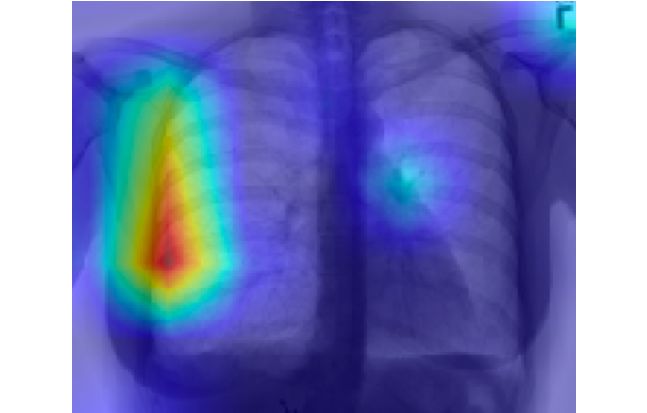

CAM 是一种可视化图片在 CNN 中最后的卷积层上被「注意」区域的方法。请注意,CAM 可视化适用于在最终全连接层之前具有全局平均池化层的架构,其中我们输出最后一个卷积层上每个单元的特征映射的空间平均值。

CAM 有效地高亮了输入图像中分配特定类别标签最重要的部分。也可以直观地说:一个类的 CAM 是基于每个特征图,将图像分配给该类的重要性。CNN 中的特征映射反映了图像中特定视觉图案(即特征)的存在。我们通过对特征映射的重要性加权的特征映射和来计算 CAM。因此,在重要信道中具有更大激活的输入图像的区域在 CAM 中被赋予了更大的权重,因此显得「更热」。

在气胸分类器的背景下,这相当于强调胸透照片中识别(或未识别到)气胸最为重要的那些像素。

最终特征图上的类激活映射

在对最终的类激活图进行上采样以后,我们可以把胸透照片中与气胸检测最相关的区域可视化(至少是从神经网络的角度看)。

气胸阳性的胸透照片类激活图

正如气胸阳性的胸透照片示例所展示的那样,CAM 最终可以可视化为一张热图。